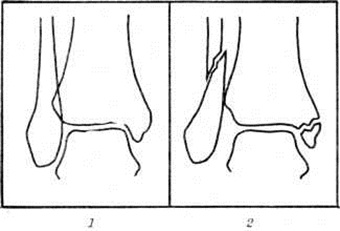

Дюпюитрена переломДюпюитрена перелом (G. Dupuytren, франц. хирург, 1777— 1835) — перелом медиальной лодыжки и малоберцовой кости в нижней трети с разрывом связок межберцового синдесмоза. При этом переломе нередко наступает подвывих стопы кнаружи. Дюпюитрена перелом встречается часто; описан Г. Дюпюитреном в 1819 год. Механизм возникновения этого перелома — пронационно-абдукционный. Стопа имеет естественную вальгусную установку, равную 10°, и поэтому она при травмах чаще подвёртывается кнаружи. При этом в силу крепости медиальной (дельтовидной) связки наступает отрывной перелом медиальной лодыжки, а таранная кость приобретает вальгусное положение. Блок таранной кости упирается в латеральную лодыжку, и происходит её перелом с разрывом передней или чаще обеих межберцовых связок. Клиническая картинаПри Дюпюитрена перелом обычно определяется припухлость в области голеностопного сустава. В случае подвывиха стопы кнаружи имеется патологический вальгусная установка стопы, особенно чётко видимая при осмотре сзади. Пальпаторно определяется резкая болезненность в области медиальной лодыжки, по ходу малоберцовой кости и в области межберцового синдесмоза. Активные и пассивные движения в суставе резко болезненны и ограничены. На рентгенограмме в прямой проекции при Дюпюитрена перелом хорошо видна линия перелома медиальной лодыжки, обычно проходящая на уровне суставной щели, а также латеральной лодыжки на уровне суставной щели или выше неё. Вместе с тем отчётливо выступают смещение отломков и возможный диастаз, то есть расхождение «вилки» сустава (рисунок 1 и 2). Для диагностики разрыва нижнего межберцового синдесмоза большое значение имеет сравнительное изучение переднезадних снимков (сделанных на одной плёнке) обоих голеностопных суставов в обычной укладке или с симметричной внутренней ротацией на 27°. Наружный подвывих стопы распознается на основании увеличения или расширения щели между суставным контуром медиальной лодыжки и прилежащей к ней суставным краем таранной кости, в норме равной ширине остальной части суставной щели голеностопного сустава. На боковой рентгенограмме обычно отчётливо видна плоскость перелома малоберцовой кости и характер смещения отломков. Линия перелома чаще всего имеет косое направление сверху вниз и сзади наперёд, а сам перелом — оскольчатый и нередко является внесуставным. Кроме этого, на боковой рентгенограмме обычно виден характер смещения медиальной лодыжки. Тщательного изучения требует снимок в боковой проекции для распознавания перелома переднего или заднего края эпифиза большеберцовой кости и соответствующего подвывиха стопы в голеностопном суставе, что очень важно для правильной репозиции отломков. |